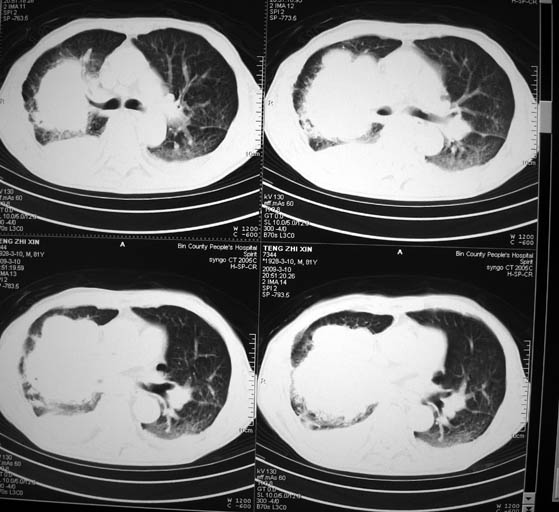

标题: CT18642:男,81岁,发热待查。

男,81岁,发热待查,右侧是占位还是膈疝?

右肺中央型肺癌并胸水。

右肺中央型肺癌并两侧胸水,左肺转移,腹水

1)考虑右肺下叶中央型肺癌并左肺转移。2)两肺上叶结核(陈旧性)。3)双侧胸腔积液。4)腹水。

右肺癌并双肺及胸膜转移。

右中央型肺癌并双肺及胸膜、肝脏转移

支持,肿块巨大,内有钙化\\坏死,肺肉瘤要考虑

很明显的排除膈疝。考虑右肺中央型肺癌,建议增强。胸腔恶性胸水。